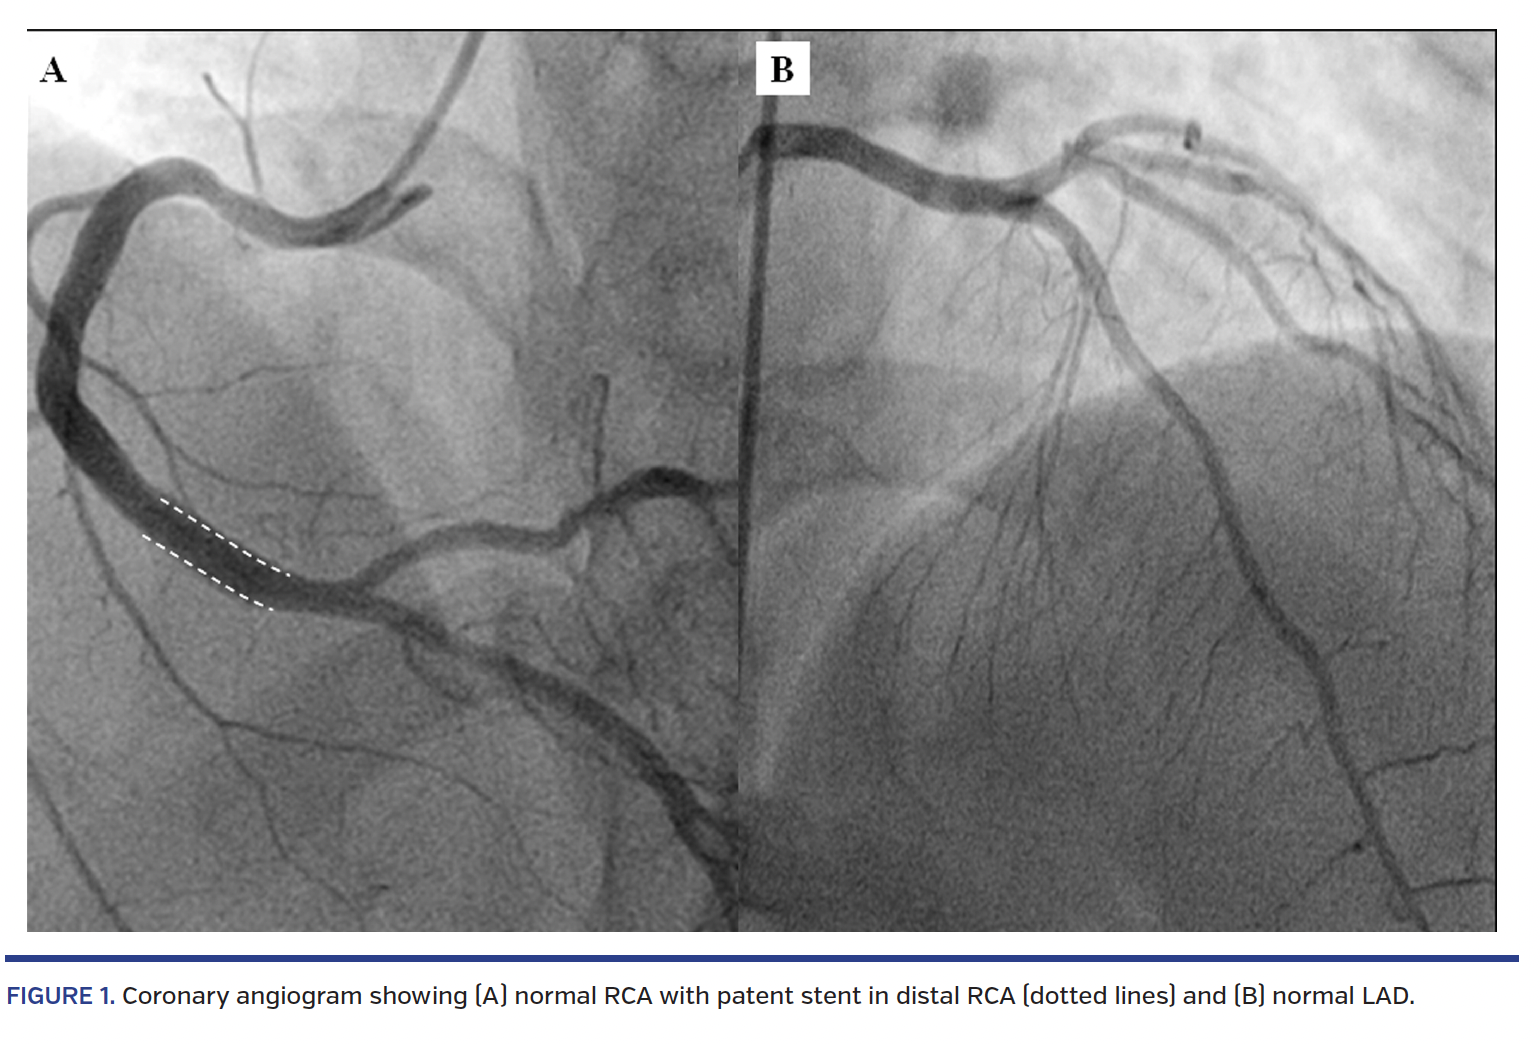

A 48-year-old hypertensive, non-smoker male had undergone drug-eluting stent implantation in the right coronary artery (RCA) 8 months prior. He presented with recurrent angina of 2-month duration. Resting electrocardiogram and echocardiogram were normal. The patient was taken up for coronary angiogram, which showed normal coronaries with patent distal RCA stent (Figure 1A; Video 1). As the left circumflex artery was not visible during left coronary angiogram (Figure 1B), the possibility of an anomalous origin from the right sinus was considered. While probing the right sinus, the patient complained of severe chest pain. Immediate RCA angiogram revealed subtotal occlusion of the RCA abutting the proximal end of the stent, with TIMI I flow (Figure 2A; Video 2) that responded quickly to 200 µg intracoronary nitrates (Figure 2B; Video 3). The diagnosis of vasospastic angina was made. The patient was discharged on nitroglycerin and diltiazem, and is doing well at 1 year of follow-up, with no recurrence of angina.